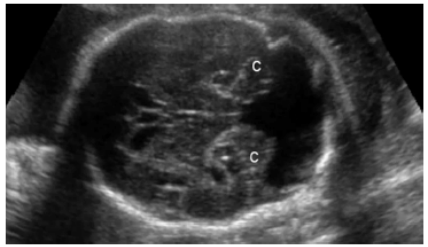

O médico ultrassonografista realizou exame ecográfico obstétrico em uma gestante de 36 semanas e 5 dias, e deparou-se com a seguinte imagem:

Hipoplasia ou agenesia do vérmis cerebelar e dilatação do quarto ventrículo, com formação cística na fossa posterior.

Essa imagem permite afirmar que o feto apresenta